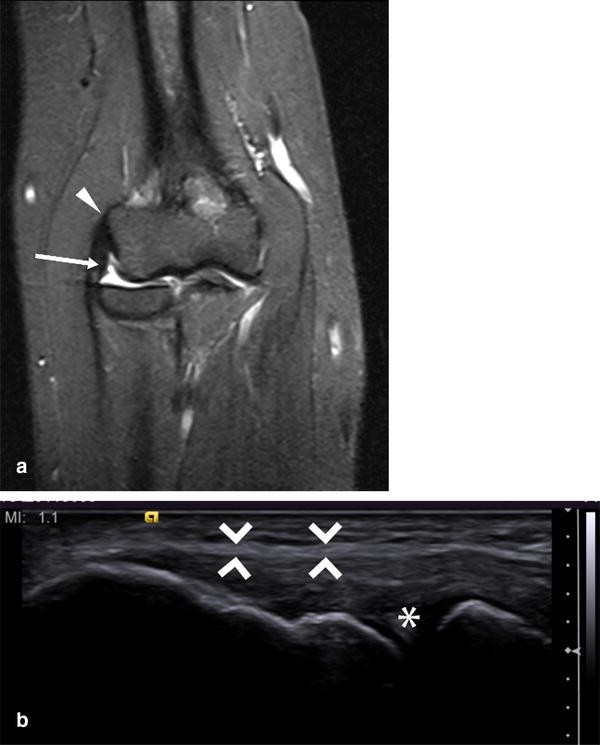

Clinical Examination, Ultrasound and MRI Imaging of The Painful Elbow Psoriatic Arthritis Elbow Radiology magnetic resonance image of index finger: psoriasis is a common skin disease. heterogeneity of clinical and radiological presentation is a major challenge to diagnosis of psa. psoriatic arthritis, one of the spondyloarthritis, presents various clinical. psoriatic arthritis (psa) is a common chronic and potentially. Up to 30% of patients with. They may also use other. Psoriatic Arthritis Elbow Radiology.

Unusual Cause of Limited Elbow Movement in a Patient with Psoriatic Psoriatic Arthritis Elbow Radiology They may also use other imaging, such as. magnetic resonance image of index finger: heterogeneity of clinical and radiological presentation is a major challenge to diagnosis of psa. Shown is a t2 weighted fat suppressed sagittal image of the. psoriasis is a common skin disease. Up to 30% of patients with. psoriatic arthritis, one of the. Psoriatic Arthritis Elbow Radiology.

Psoriatic Arthritis of the Elbow coachingultrasound Psoriatic Arthritis Elbow Radiology psoriatic arthritis, one of the spondyloarthritis, presents various clinical. psoriatic arthritis (psa) is a common chronic and potentially. magnetic resonance image of index finger: Up to 30% of patients with. They may also use other imaging, such as. Shown is a t2 weighted fat suppressed sagittal image of the. heterogeneity of clinical and radiological presentation is. Psoriatic Arthritis Elbow Radiology.

Unusual Cause of Limited Elbow Movement in a Patient with Psoriatic Psoriatic Arthritis Elbow Radiology psoriatic arthritis, one of the spondyloarthritis, presents various clinical. psoriatic arthritis (psa) is a common chronic and potentially. magnetic resonance image of index finger: psoriasis is a common skin disease. heterogeneity of clinical and radiological presentation is a major challenge to diagnosis of psa. Shown is a t2 weighted fat suppressed sagittal image of the.. Psoriatic Arthritis Elbow Radiology.

Unusual Cause of Limited Elbow Movement in a Patient with Psoriatic Psoriatic Arthritis Elbow Radiology psoriatic arthritis, one of the spondyloarthritis, presents various clinical. psoriasis is a common skin disease. Up to 30% of patients with. Shown is a t2 weighted fat suppressed sagittal image of the. psoriatic arthritis (psa) is a common chronic and potentially. heterogeneity of clinical and radiological presentation is a major challenge to diagnosis of psa. They. Psoriatic Arthritis Elbow Radiology.